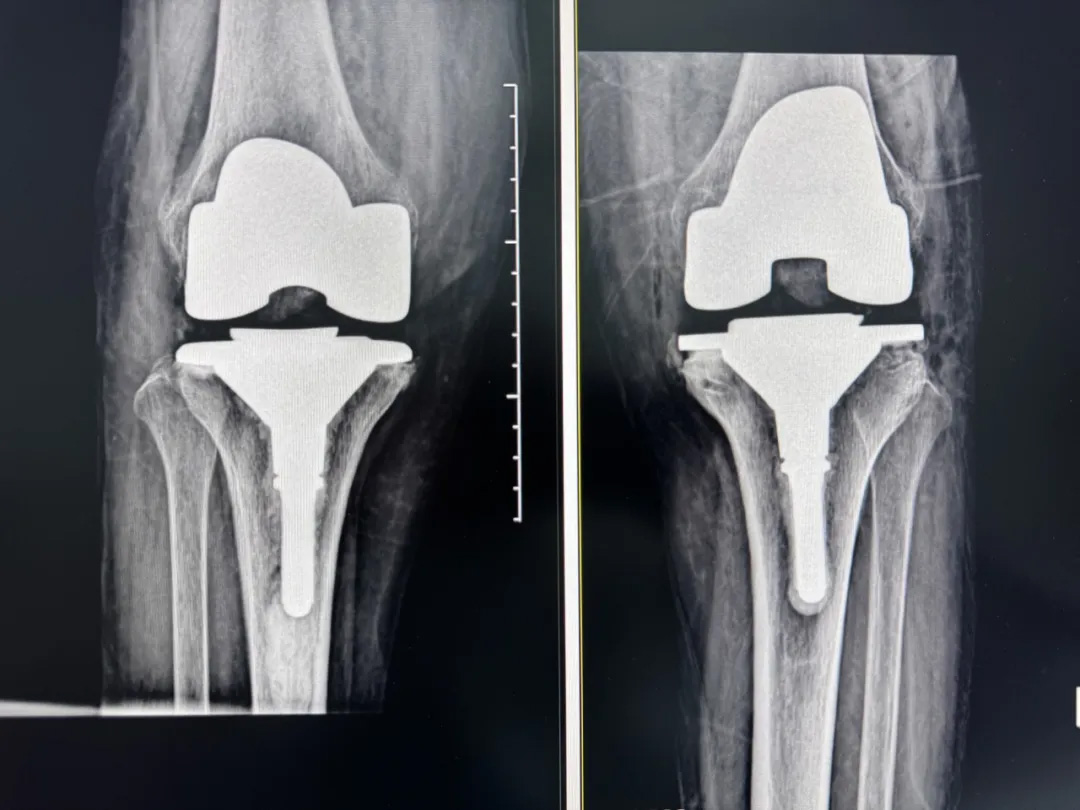

術(shù)后:當(dāng)天鄭阿婆即開始抬腿的康復(fù)訓(xùn)練,24小時內(nèi)扶助行器下地行走,三天后已能在病房走廊獨(dú)立行走,完成洗漱用餐

兩周后健步出院時,女兒含淚感慨“之前擔(dān)心她年紀(jì)大扛不住手術(shù),沒想到恢復(fù)這么快!現(xiàn)在每天散步比我還精神。知道技術(shù)這么先進(jìn),真該早點(diǎn)來!”

圖片